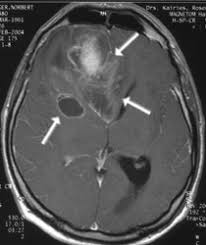

Ранняя диагностика глиобластомы: ключ к спасению Глиобластома – это одна из самых агрессивных и распространенных форм первичных опухолей мозга.

Ранняя диагностика глиобластомы: как распознать и победить Глиобластома — одно из самых агрессивных и сложных для лечения онкологических заболеваний мозга․